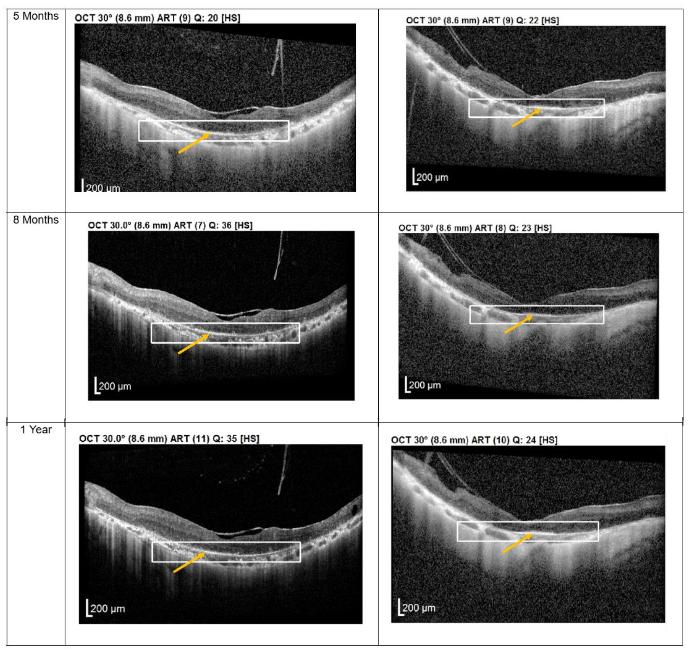

Figure 2. Optical coherence tomography (OCT) images for both eyes of Patient 2 from pre-injection up to 11 month follow-up. Orange arrow demonstrates the presence of hyperreflective material at the interdigitation area of the photoreceptors at the macula and extramacular region. These were observed and maintained until the last follow-up examination.

Both patients received a total of seven mesenchymal stem cell (MSC) transplantations, administered every 4-6 weeks, with follow-up from November 2020 to November 2022. Both patients reported no deterioration in vision since the first subtenon implantation in November 2020. Optical coherence tomography (OCT) images consistently demonstrated the maintenance of a hyperreflective region, with no notable increase in intensity. The previously reported improvements in visual function remained stable throughout the two-year follow-up, with no evidence of regression.

Importantly, no severe ophthalmic or systemic complications were observed during this period, supporting the safety of subtenon MSC therapy over a prolonged follow-up. No serious adverse effects were reported by either patient.

Structural changes observed on optical coherence tomography (OCT) provide additional insight into the biological effects of treatment. All patients demonstrated persistent hyperreflective material localized at the interdigitation zone of the photoreceptors. Rather than representing fibrotic change, this OCT finding may reflect photoreceptor outer segment remodeling, improved mitochondrial activity, or enhanced metabolic integrity of surviving photoreceptors. Similar hyperreflective changes have been reported in studies evaluating MSC-mediated neuroprotection and are often associated with functional stabilization rather than disease progression. The stability of these OCT findings over extended follow-up in patients 1 and 2 suggests a sustained therapeutic effect rather than a transient inflammatory response.